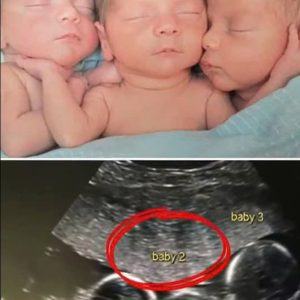

The day my wife Emily and I left the doctor’s office should have been one of the happiest moments of our lives. We had waited, hoped, and prayed for months to hear the…